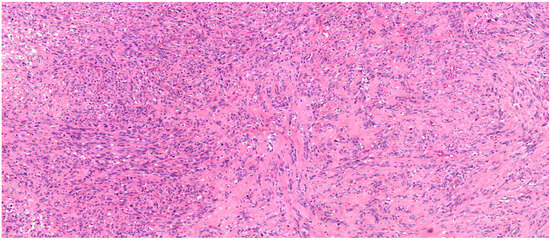

2.1. Histology Results

IDCS is a malignant neoplasm composed of spindle to epithelioid cells, displaying morphological and immunophenotypic characteristics similar to interdigitating dendritic cells. The tumour cells are characterised by a diffuse expression of S100 and histiocytic markers, while lacking expression of Langerhans cell markers (such as CD1a and langerin). During the histological examination of the lymph nodes, storiform spindle cells, tumorous giant cells, and atypical mitoses were identified (Figure 3). Immunohistochemical reactions demonstrated that the tumour cells were positive for S-100 and SOX10 (Figure 4), with variable, focal positivity for LCA, CD4, and CD68 (Figure 5). LCA involves detecting CD45 expression on cell surfaces to diagnose lymphomas and other haematolymphoid neoplasms, thereby distinguishing them from non-haematopoietic tumours such as carcinomas, sarcomas, and melanomas. The observation of focal positivity indicates the presence of a non-lymphoid tumour. Based on the histomorphology and CD68 positivity, as well as the absence of melanocyte-specific antigens (HMB-45, Figure 6), the tumour was determined not to correspond to metastatic malignant melanoma. This indicates that the cells did not show HMB-45 protein, which is typically found in melanocytes. Consequently, other types of melanoma, such as desmoplastic malignant melanoma or non-melanocytic tumours, should be considered. However, the S-100 reaction produced positive results. S-100 is a tumour marker typically associated with malignant melanoma and is detected in the majority of melanoma subtypes, including desmoplastic melanoma. It is known for its high sensitivity in identifying melanoma. Since the S-100 reaction was positive and HMB-45 tests returned negative results, we can conclude that there is no lymph node metastasis from malignant melanoma. SOX-10 is a strong indicator of both benign and malignant melanocytic cells; however, it can also be observed in other tumours, such as fibrohistiocytic proliferations, nerve sheath tumours, and epithelial tumours. To rule out lymphomas and other malignancies associated with EBV infection, the EBER-ISH reaction was performed, which yielded negative results (Figure 5). Ultimately, the final diagnosis was determined to be IDCS, a second independent tumour distinct from the initially diagnosed malignant melanoma, which originated from the lymph nodes of the submandibular salivary gland.

Figure 3. The HE stained section represents a cross-section of a lymph node with altered architecture. Pleomorphic spindle or epithelioid cells are arranged in fascicles, whorls, or sheet-like patterns. A hyalinised stroma with embedded elongated tumour cells is observed.